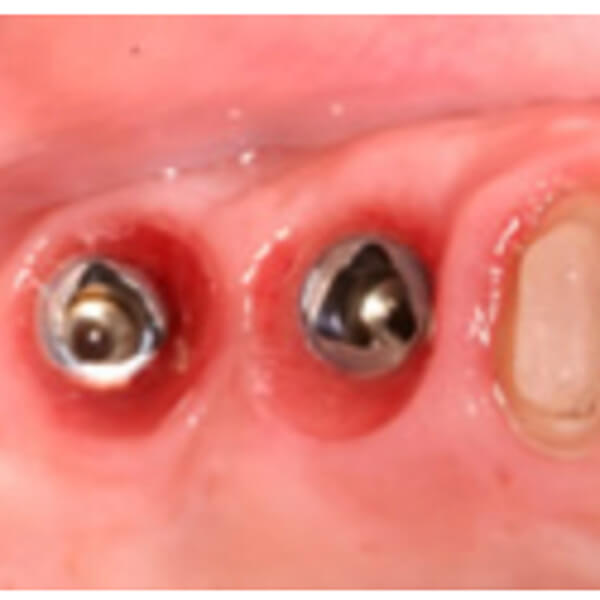

インプラント義歯とは?

インプラント義歯

あごの骨にインプラント(ネジのようなものを埋め込んだもの)をうえて、そのインプラントを土台として入れ歯を装着する方法です。インプラントを片あごに4本埋入して、アタッチメントを取り付けます。

入れ歯をしっかりと固定することができ、入れ歯のがたつきにより発生する痛みもありません。(インプラントの必要本数が確保できない場合や、治療時間・金銭面の負担を軽減させたい時)